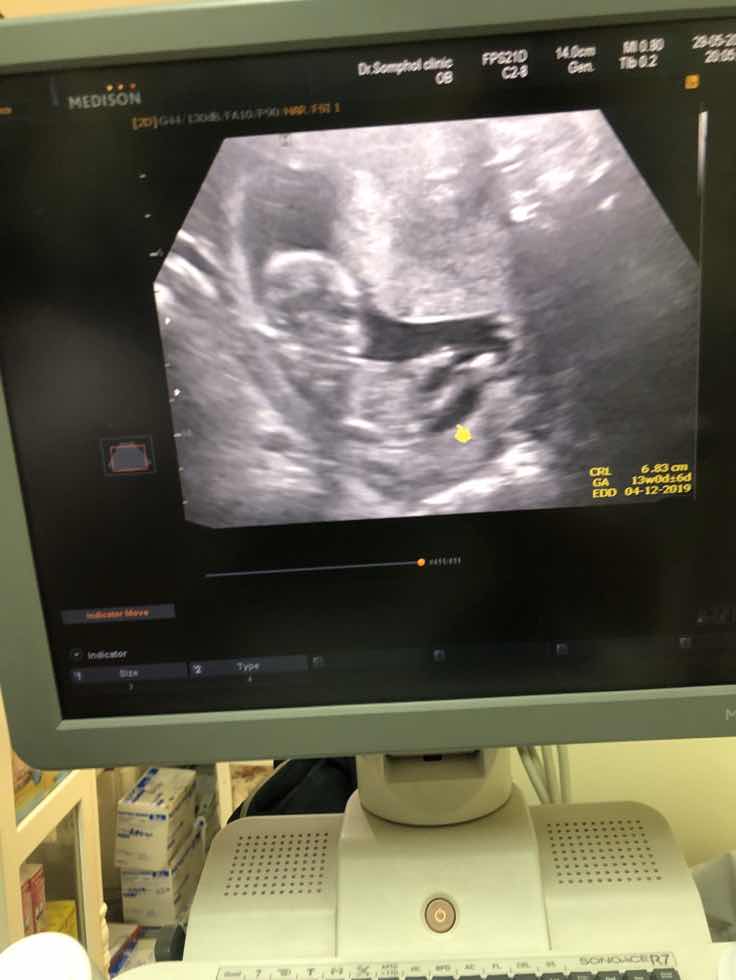

13w ค่ะ